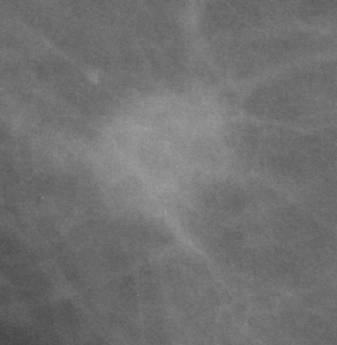

5.3 Interpretability

Deep learning models often lack interpretability and as such are hard to adopt for practical use in medical settings. [21] describe a methodology to visualize saliency maps which show the regions of an image the network is sensitive to when making predictions. This is performed by computing the gradient of the image with respect to the unnormalized class scores. Regions with larger gradient indicate higher contribution to the prediction (brighter in Fig. 3). Both the AlexNet and GoogLeNet learn to attend to the edges of the mass, which is a high-signal criterion for diagnosis, while also paying attention to context.